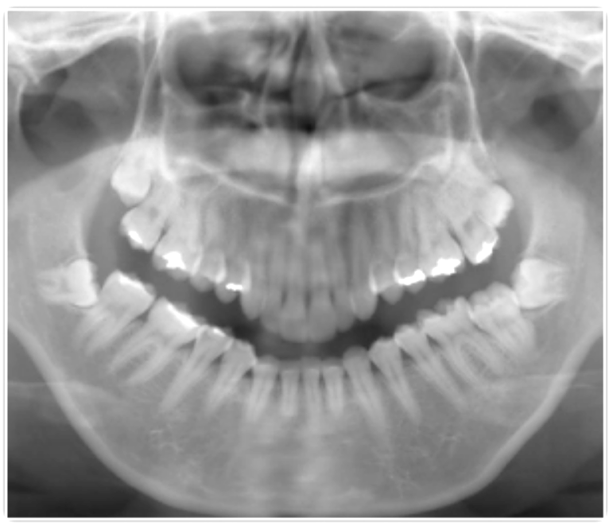

難しいケースはCTスキャンにより精査します。